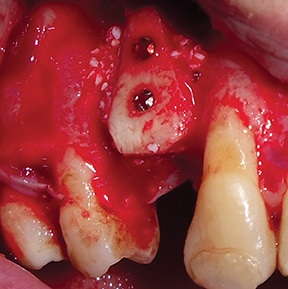

After a four-month healing period, a full-thickness flap was raised to evaluate the outcome (Fig. 21).

After removing fixation screws (Fig. 22), a 3.75 × 13 mm implant was placed with a final torque >35 N·cm (Figs. 23–24) and the flap was closed with 4-0 monofilament interrupted sutures (Fig. 25).

Fig. 21: Full-thickness flap raised at surgical re-entry

Block by Block

Fig. 22: Removal of fixation screws